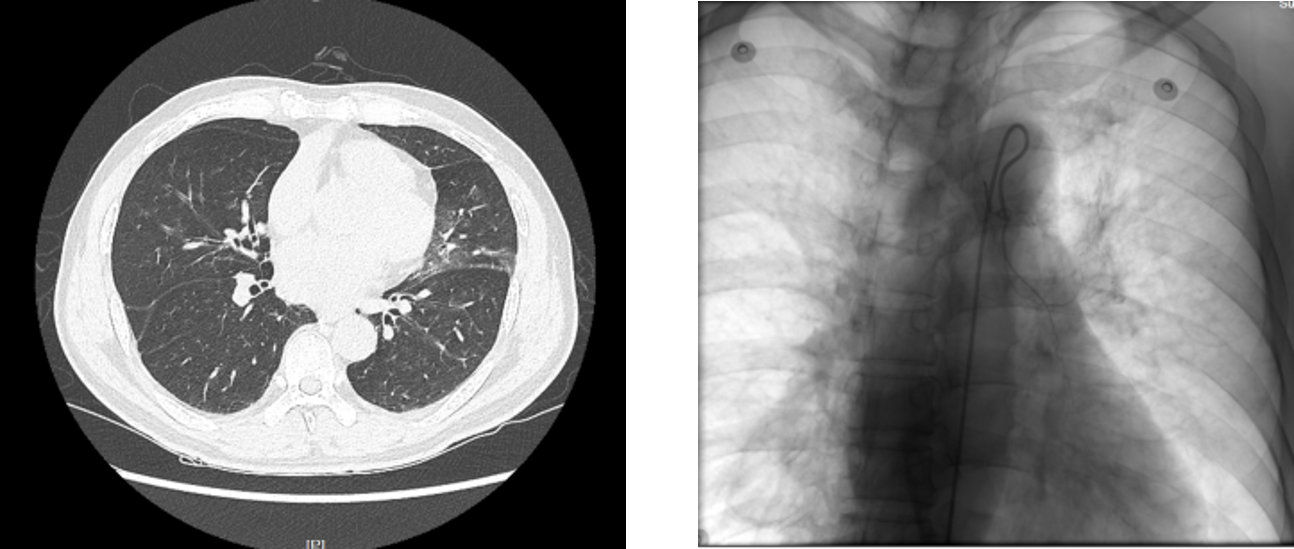

该患者有支气管扩张,同时合并房颤、高血压病、糖尿病等诸多基础疾病。1个多月前,患者开始出现咯血症状,每天4-5次、量少,在当地医院保守止血治疗后好转。7月27日凌晨3:30,患者第一次出现大咯血,经介入与血管外科副主任医师程龙团队急诊行支气管动脉栓塞术后症状好转。现患者再次出现大咯血,生命体征不稳定,面罩给氧、药物止血、介入栓塞等治疗均无法缓解。麻醉手术科主任李健团队及时到场,为患者实施了双腔气管插管接呼吸机辅助通气。我科副主任曾大雄进行了第一次床旁支气管镜探查,见左侧左支气管内大量鲜血及血凝块堵塞,已经完全堵塞左侧呼吸道和右侧中、下叶支气管、考虑左肺出血可能性大。曾医生在支气管镜下清理右侧气道,清除后未见活动性出血,明确出血位于左侧肺。此时患者生命体征暂时平稳,为患者移动至手术室创造了机会。但左主支气管内出血仍无法解决,危险仍未解除,此时和胸心大血管外科主任马海涛商讨患者的治疗方法,团队一致认为唯有手术切除出血病变,且手术之前,需要明确出血部位。但是,清理左肺血块导致出血的可能性很大,若再次出血,随时会威胁到患者的生命。

为此,呼吸与危重症医学科、胸心大血管外科和麻醉手术科联合制定了一整套抢救方案和预案。我院党委书记、院长侯建全在了解到该病人的情况后,高度重视、亲自关心,并要求各科室全力以赴抢救病人。蒋军红主任进行了第二次支气管镜检查,调整双腔气管插管,见左主支气管被血栓完全堵住,利用活检钳、冷冻等多种方法逐步清除左主、左下叶背段及基底段血栓,见管腔基本通畅。耗时1个多小时,最后清理左上叶开口血栓时,突发再次活动性出血。确认出血来至于左上叶,转交胸心大血管外科行左上叶切除术。马海涛主任随即实施了胸腔镜辅助小切口左上肺叶切除术、心包内处理。马主任凭借娴熟的手术操作,最终化险为夷,左上叶肺叶顺利切除,患者出血停止。胸心大血管外科手术后,仍需清除气道血凝块,便于左肺膨胀,并降低后续感染的风险,故外科医生完成手术后,呼吸与危重症医学科医生又再次在支气管镜下清理气道内残余血凝块。当这一切完成后,已经是晚上8点多钟。所有参与抢救的医务人员才长舒一口气,“终于救过来了”。